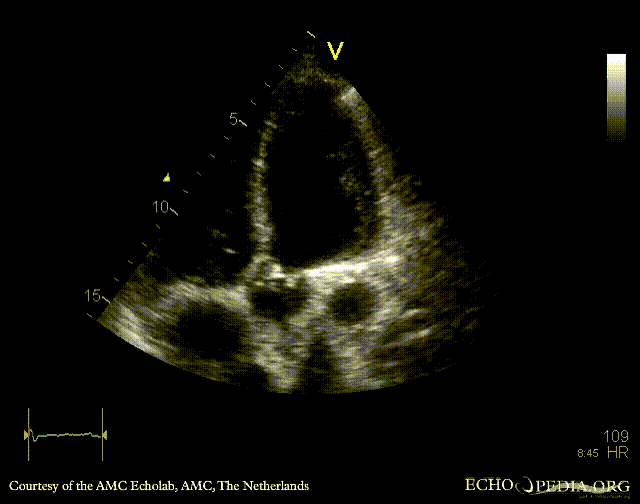

PLAX with Color Doppler: severe aortic regurgitation A4CH: dilated atria and ventricles, poor function of left ventricle